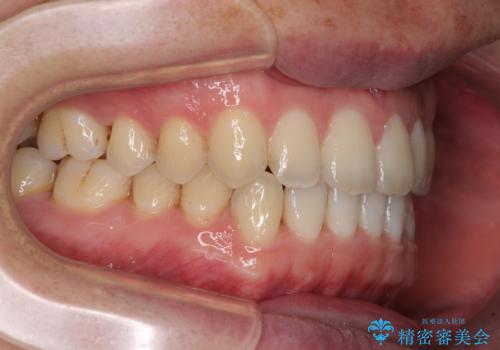

すきっ歯の改善 インビザライン矯正治療

- 上の前歯の隙間を気にして来院された患者様です。

インビザラインにより、上下の歯列を側方に拡大しつつ、前歯の隙間を閉じていくこととしました。

1日22時間の装着時間をしっかりと守ってくださったので、隙間がきれいに閉じ、口元の突出感も改善することができました。